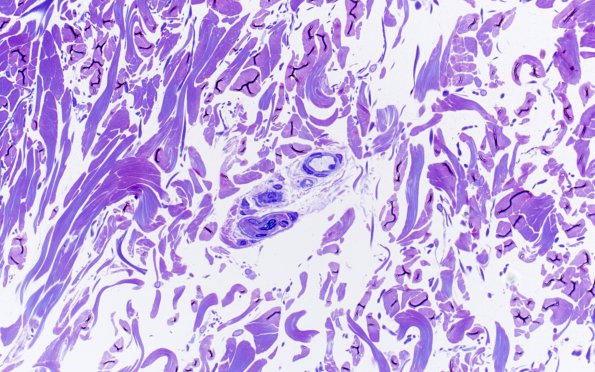

One small peripheral nerve fascicle in this skin biopsy is accompanied by several small vessels. These small arteriolar vessels do not exhibit an internal elastic lamina but do have multiple layers of smooth muscle and, subsequently illustrated, have GOMs. (Toluidine blue stained 1 micron thick plastic section) (Toluidine blue stained 1 micron thick plastic section)